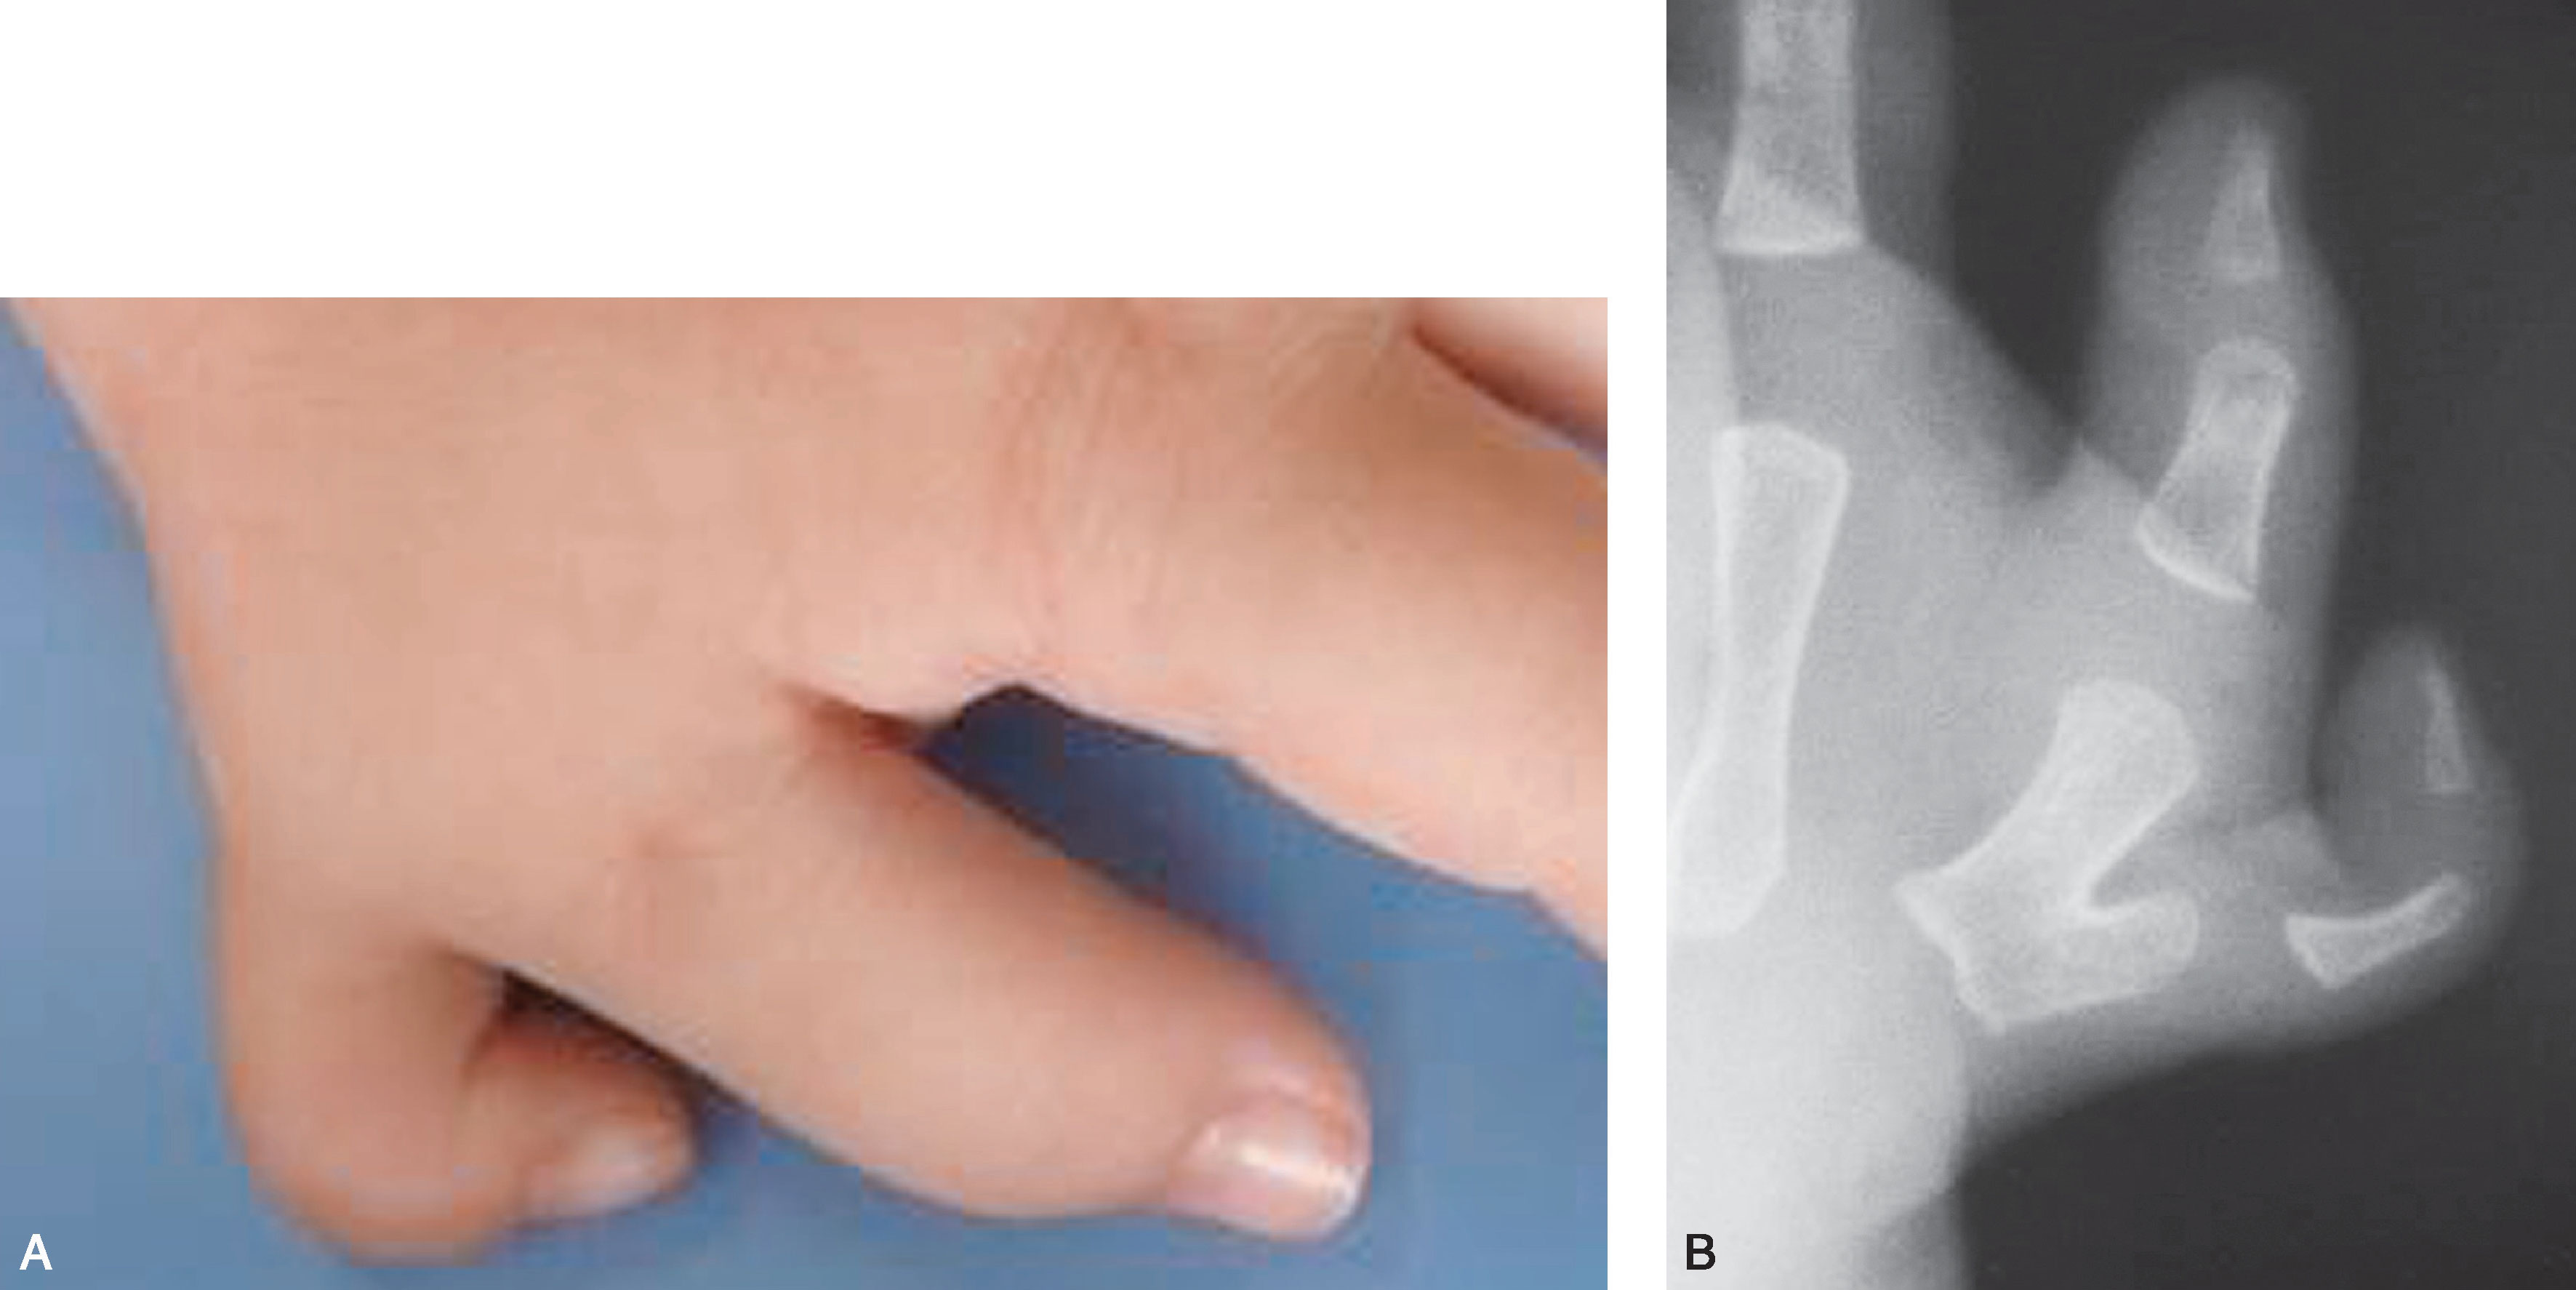

图2-1-4 Ⅰ型病例4

A.“镜影拇指”,主、次拇指外形及大小几乎一致;B.X 线片显示主、次拇指远节指骨几乎等大,是主、次拇指融合的适应证。 也可切除桡侧拇指,保留尺侧拇指,同时行保留的尺侧远节指骨基底骨骺端的桡侧闭合楔形截骨,但需保护骨骺板